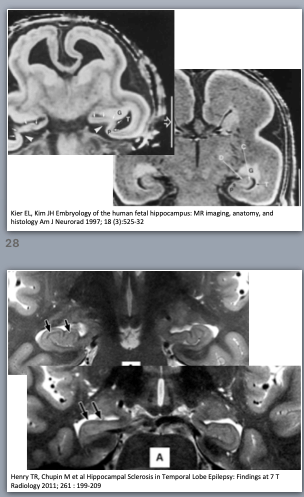

The hippocampus is the phylogenetically oldest part of brain cortex, consisting of only 3 layers and termed archicortex or archipallium. It consists of two interlocking gyri, the dentate gyrus and Ammon’s horn, and the subiculum. The hippocampus plays an important role in learning and memory, and also influences the hypothalamus. Precursor cells in the dentate gyrus keep forming new neurons (neurogenesis) during the entire human life, playing a role in the synaptic plasticity for learning and memory (15). The neighbouring parahippocampal gyrus and olfactory system are a little bit younger and are called paleocortex or paleopallium, consisting of 4 or 5 layers.

Figure 3. Hippocampus and amygdala on coronal IR image from the temporal lobe